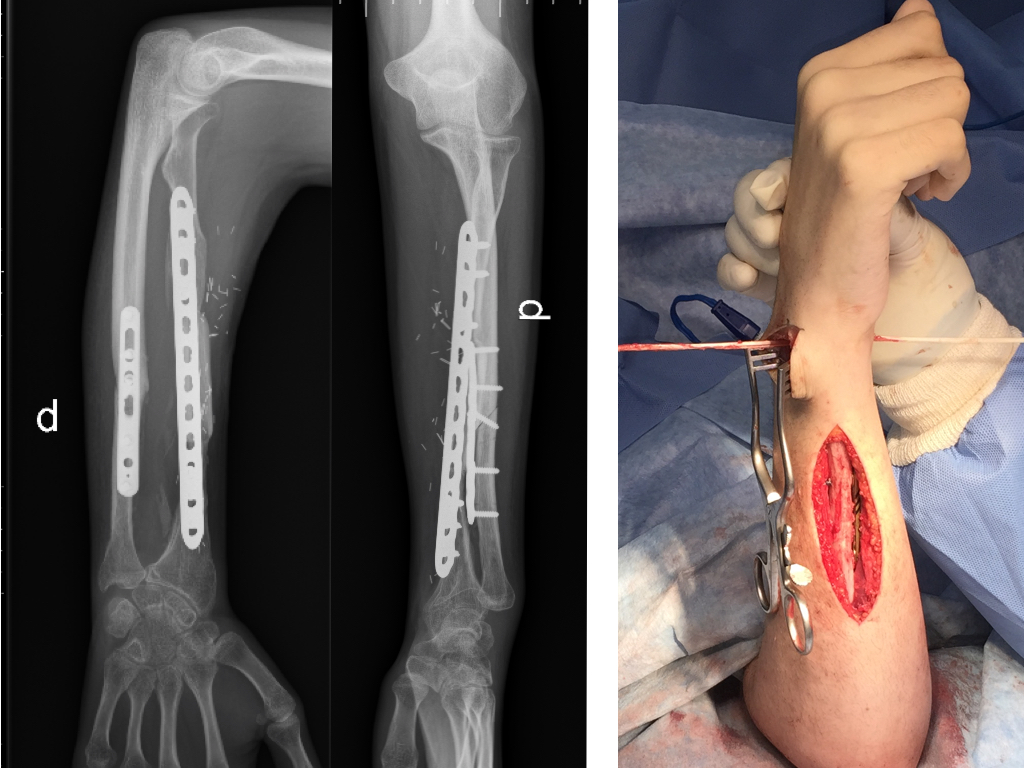

Introducción Los defectos óseos mayores a 6 cm en los huesos largos resultan en un problema difícil a reconstruir del miembro superior. Entre las opciones se encuentran: el injerto óseo alogénico, la utilización de la técnica de Masquelet y el injerto vascularizado de peroné. El peroné vascularizado se ha convertido en el principal método de reconstrucción por sus ventajas biológicas. El objetivo del presente estudio fue evaluar la tasa y el tiempo de consolidación ósea y las complicaciones asociadas en una serie continua de pacientes.  Material y MétodosSe realizó una revisión del registro para identificar a todos los pacientes que se sometieron a una reconstrucción con peroné vascularizado durante un periodo de 5 años. Se incluyeron a todos los pacientes que fueron tratados por defectos mayores de 6cm en miembro superior y se excluyeron aquellos en que la reconstrucción se llevó a cabo en el miembro inferior o como técnica asociada para aumentación de la estabilidad en artrodesis de hombro. Se analizaron variables preoperatorias, intraoperatorias y postoperatorias inmediatas y alejadas.  Resultados  Durante el periodo de evaluación, 18 pacientes fueron sometidos a cirugías reconstructivas con IVP. Seis pacientes (4 hombres/2 mujeres) cumplían con los criterios de inclusión. La edad promedio fue de 47 años (rango 16 a 66 años). En promedio, los pacientes tenían 3 cirugías previas (rango 1 a 4). El tiempo transcurrido entre el trauma inicial y la cirugía reconstructiva varió de 2 a 21 años (promedio 7 años). Las causas del defecto fueron la secuela postraumática (pseudoartrosis) en cinco pacientes y la enfermedad oncológica en un paciente con diagnóstico de Tumor de Células Gigantes. Los segmentos óseos involucrados fueron el húmero (tres pacientes), radio (dos), y cubito (uno). El defecto óseo promedio fue de 10 cm (rango 6 a 15 cm). En cuatro casos se utilizó un injerto osteocutáneo de peroné y un caso sin colgajo fasciocutáneo asociado. En todos los casos, se utilizaron placas bloqueadas como método de fijación del injerto. El tiempo de seguimiento promedio fue de 17 meses (rango de 5 a 40 meses). La consolidación ósea fue lograda en todos los casos. La consolidación ósea llevó promedio de consolidación ósea fue de 16 semanas (rango de 8 a 22 semanas). Dos pacientes sufrieron complicaciones posoperatorias. Un paciente sufrió una exposición del material de osteosíntesis. Otro paciente evolucionó con aflojamiento del material de osteosíntesis. Ninguno de los pacientes presentó complicaciones o secuelas funcionales en la zona dadora.  Conclusión El injerto óseo vascularizado de peroné es una opción válida para el tratamiento quirúrgico reconstructivo de defectos óseos segmentarios mayores a 6cm en el miembro superior con una tasa alta de consolidación, aún en casos con múltiples cirugías previas o con larga evolución de la lesión. Los detalles técnicos previenen las complicaciones en la zona dadora.